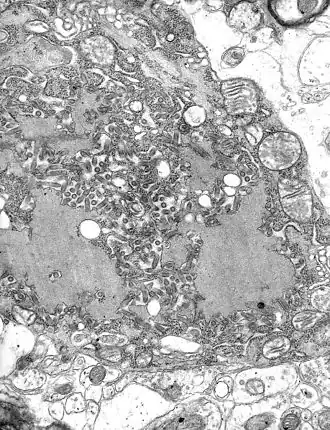

La dernière étape est le bourgeonnement des particules virales soit à travers la membrane plasmique soit à travers les membranes du réticulum endoplasmique ou du Golgi.